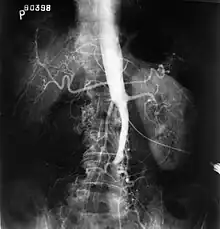

- Syndrome de Leriche : oblitération thrombotique de la bifurcation aortique[28].

- (en) avec André Morel, The Syndrome of Thrombotic Obliteration of the Aortic Bifurcation, Annals of Surgery, (lire en ligne).